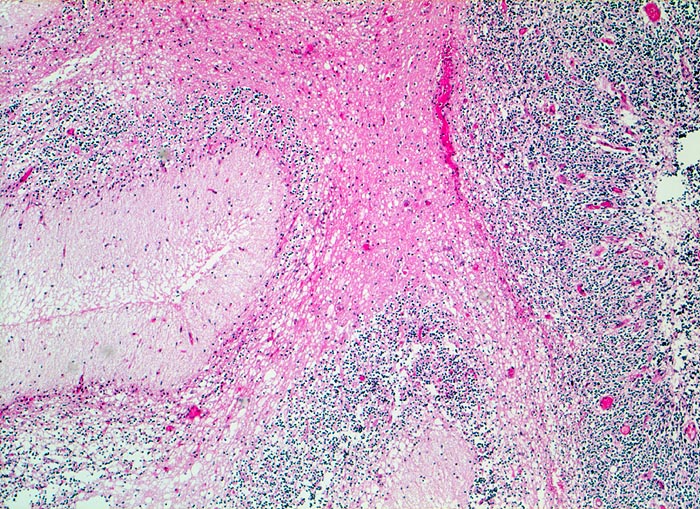

Wegen der hohen Zelldichte und der hohen Kern-Zytoplasmarelation erscheinen die Tumoren in der HE Färbung blau. Medulloblastome müssen differentialdiagnostisch von morphologisch ähnlichen kleinzelligen undifferenzierten Karzinomen und Lymphomen abgegrenzt werden. Das klassische Medulloblastom besteht aus dicht gepackten Zellen mit runden bis ovalen oder karottenförmigen stark hyperchromatischen Kernen umgeben von wenig Zytoplasma. Runde Zellen mit weniger dichtem Chromatin sind oft beigemischt. Zahlreiche Mitosen, flächenhafte Nekrosen und Apoptosen sind typisch. In weniger als einem Drittel der Fälle findet man die typischen Homer-Wright Rosetten. Diese bestehen aus ringförmig angeordneten Tumorzellkernen um ein fibrilläres Zentrum aus Zytoplasmafortsätzen.

• Scharf begrenzter rundlicher sehr zellreicher (deshalb blauer) Tumor.

• Monomorpher Zellrasen mit hyperchromatischen ovalen oder karottenförmigen Zellkernen.

• Kaum erkennbares Zytoplasma.

• Homer-Wright Rosetten aus ringförmig angeordneten Tumorzellkernen um ein fibrilläres Zentrum aus Zytoplasmafortsätzen.